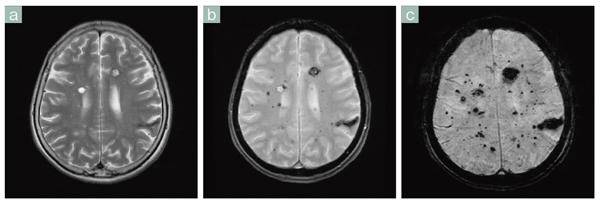

■症例4 磁化率強調画像(海綿状血管腫)

a:T2強調画像,b:T2*強調画像,c:T2*強調画像のthin sliceをMinIP処理したもの。

T2強調画像(a)では出血を伴う比較的大きな病変しか同定できないが,T2*強調画像(b)では小さな病変がたくさん確認できる。cでは,さらに小さな病変を強調して描出することができる。